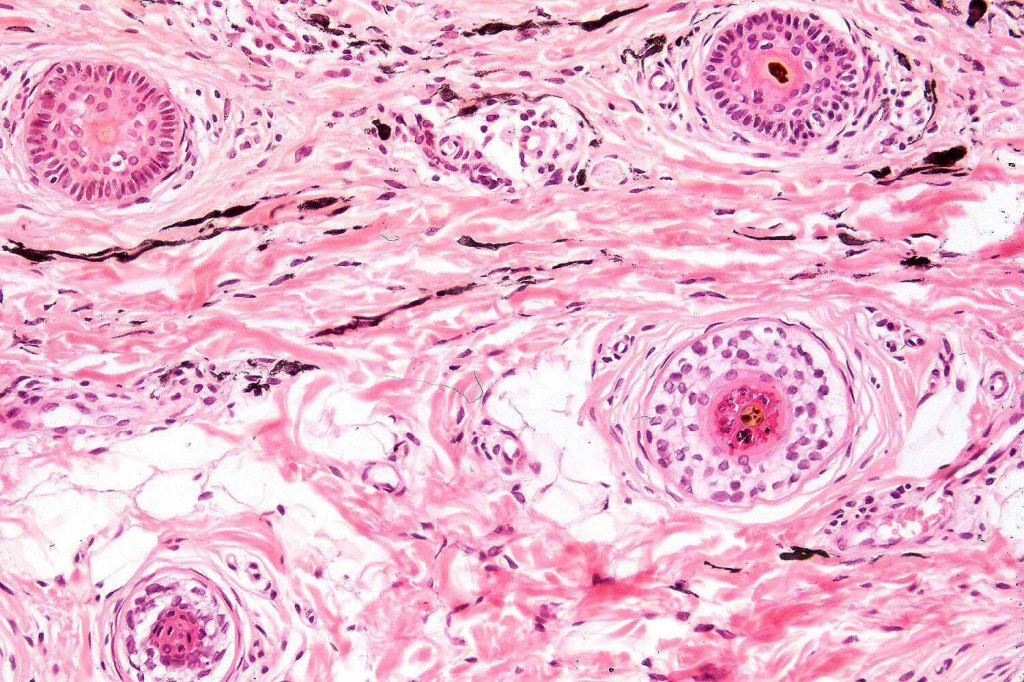

Histologically, it is characterized by a dense population of spindled, dendritic melnanocytes & melanophages with variable fibrosis. It may sometimes represent a component of a combined nevus. Mitotic activity is not usually present and pleomorphism is absent (see atypical blue nevus below). Involvement of the arrector pili muscle is not uncommon.

Very exceptionally, blue nevus also involves the epidermis (compound blue nevus).